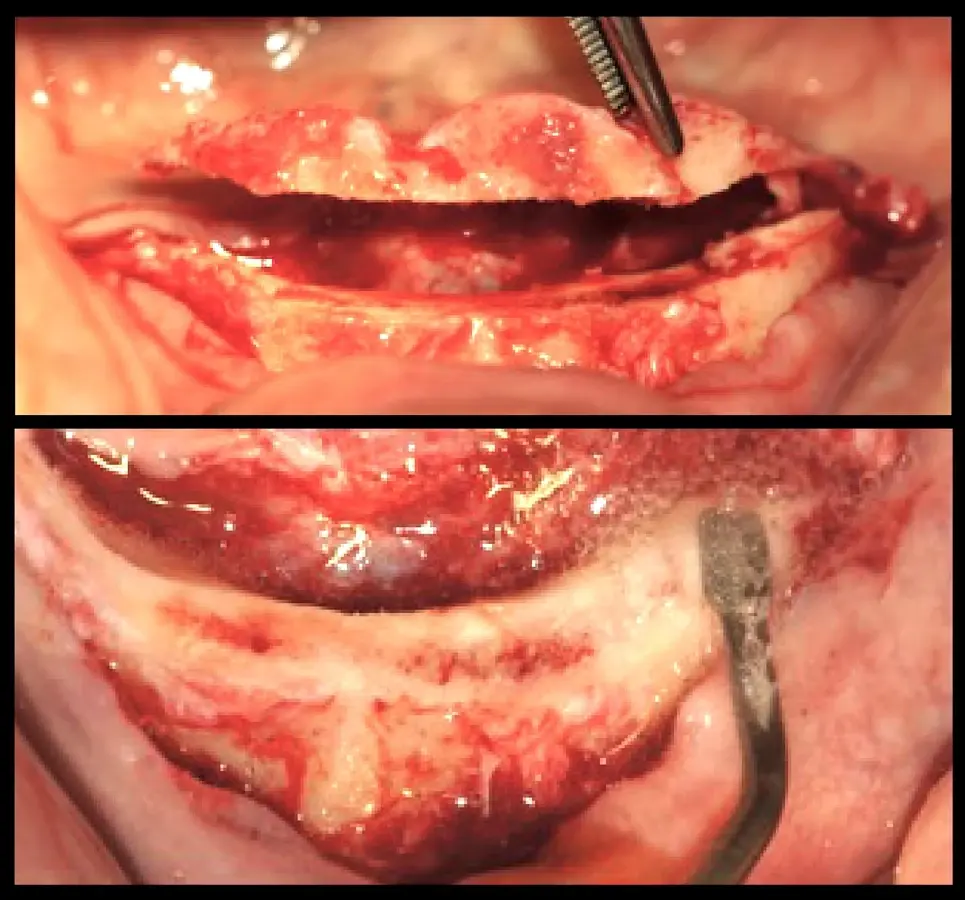

El procedimiento quirúrgico se inició con la asepsia y antisepsia del campo operatorio y del paciente. A continuación, se colocó anestesia infiltrativa a nivel de la proyección de salida de los agujeros mentonianos, se procedió con la incisión y decolado. Se realizó la delimitación y regularización del reborde óseo mediante el inserto aserrado B7 y el subsiguiente remodelado del reborde crestal mediante el inserto plano diamantado S1 del piezoeléctrico Piezomed (W&H) (Figuras 4 y 5).

Remodelado óseo

Figura 4. Remodelado óseo mínimamente traumático realizado con tecnología piezoeléctrica.

Insertos de corte y desgaste

Figura 5. Insertos de corte y desgaste que se utilizan con tecnología piezoeléctrica.